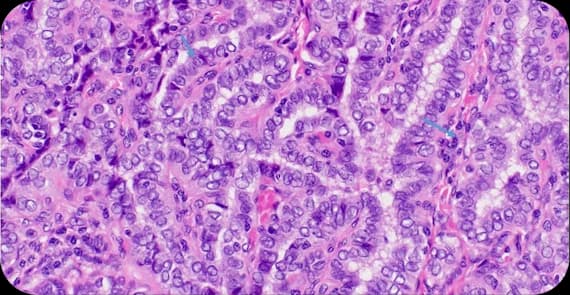

When patients ask what thyroid cancer is, the explanation begins at the cellular level. Thyroid cancer occurs when cells within the thyroid gland develop genetic mutations that lead to uncontrolled growth and division.

In many cases, the cancer presents as a small nodule in the thyroid gland. What happens in thyroid cancer is the transformation of normal thyroid cells into malignant cells that may grow locally or spread to nearby lymph nodes.

Understanding thyroid cancer classification and tumour behaviour helps determine the most suitable treatment for thyroid cancer.